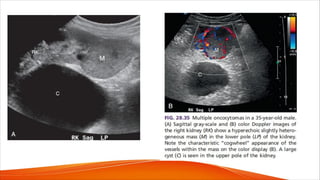

• Solid masses such as renal cell carcinoma or oncocytomas may

demonstrate significant neovascularity that is distinct from vascular

disorders such as pseudoaneurysm or AVM. For example, patients with

oncocytoma can reveal a characteristic spoke-wheel pattern of blood flow

within the tumor (Fig. 28.35).